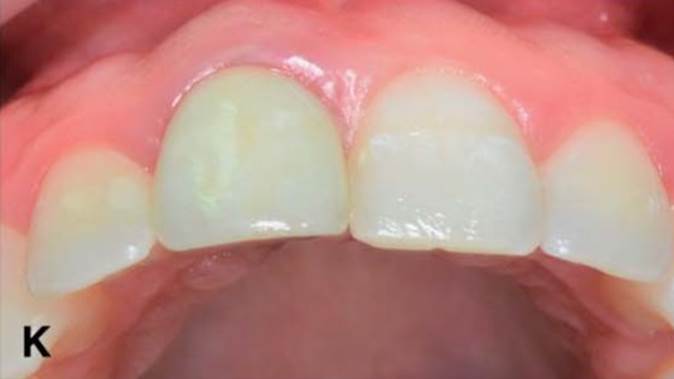

Clinical case: Replacement of fractured central incisor (#11) with immediate implant

& Root Membrane Technique

- Courtesy of Dr. Miltiadis Mitsias, Greece -

Keywords

AnyRidge, Root Membrane Technique, retrospective study, long-term study, immediate implants, bone resorption, bone preservation, Dr. Miltiadis Mitsias,survival, success, maxillary anterior, single replacement

Products:

AnyRidge implant system, Root Membrane kit